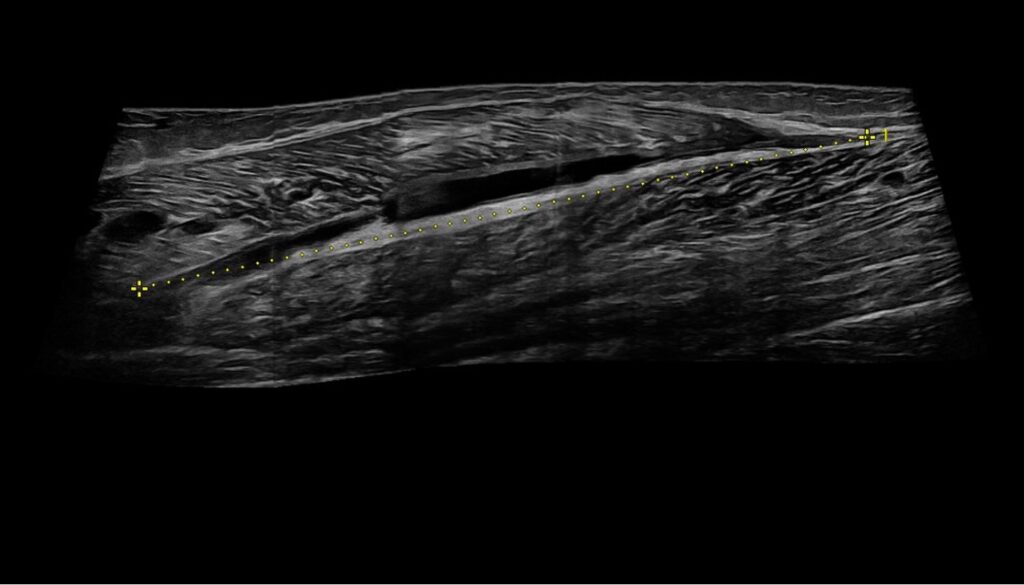

Lesioni muscolari

Lesioni muscolari: un problema frequente nello sport Le lesioni muscolari sono una problematica diffusa sia negli sport ricreativi che professionali, rappresentando dal 10% al 55%